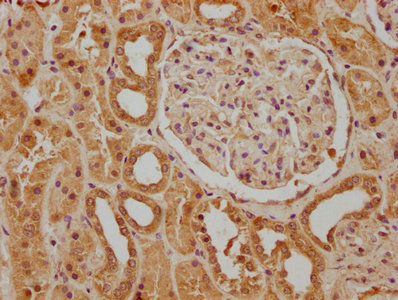

CSB-PA878932OA01HU

IHC image of CSB-PA878932OA01HU diluted at 1:400 and staining in paraffin-embedded human kidney tissue performed on a Leica BondTM system. After dewaxing and hydration, antigen retrieval was mediated by high pressure in a citrate buffer (pH 6.0). Section was blocked with 10% normal goat serum 30min at RT. Then primary antibody (1% BSA) was incubated at 4°C overnight. The primary is detected by a biotinylated secondary antibody and visualized using an HRP conjugated SP system.